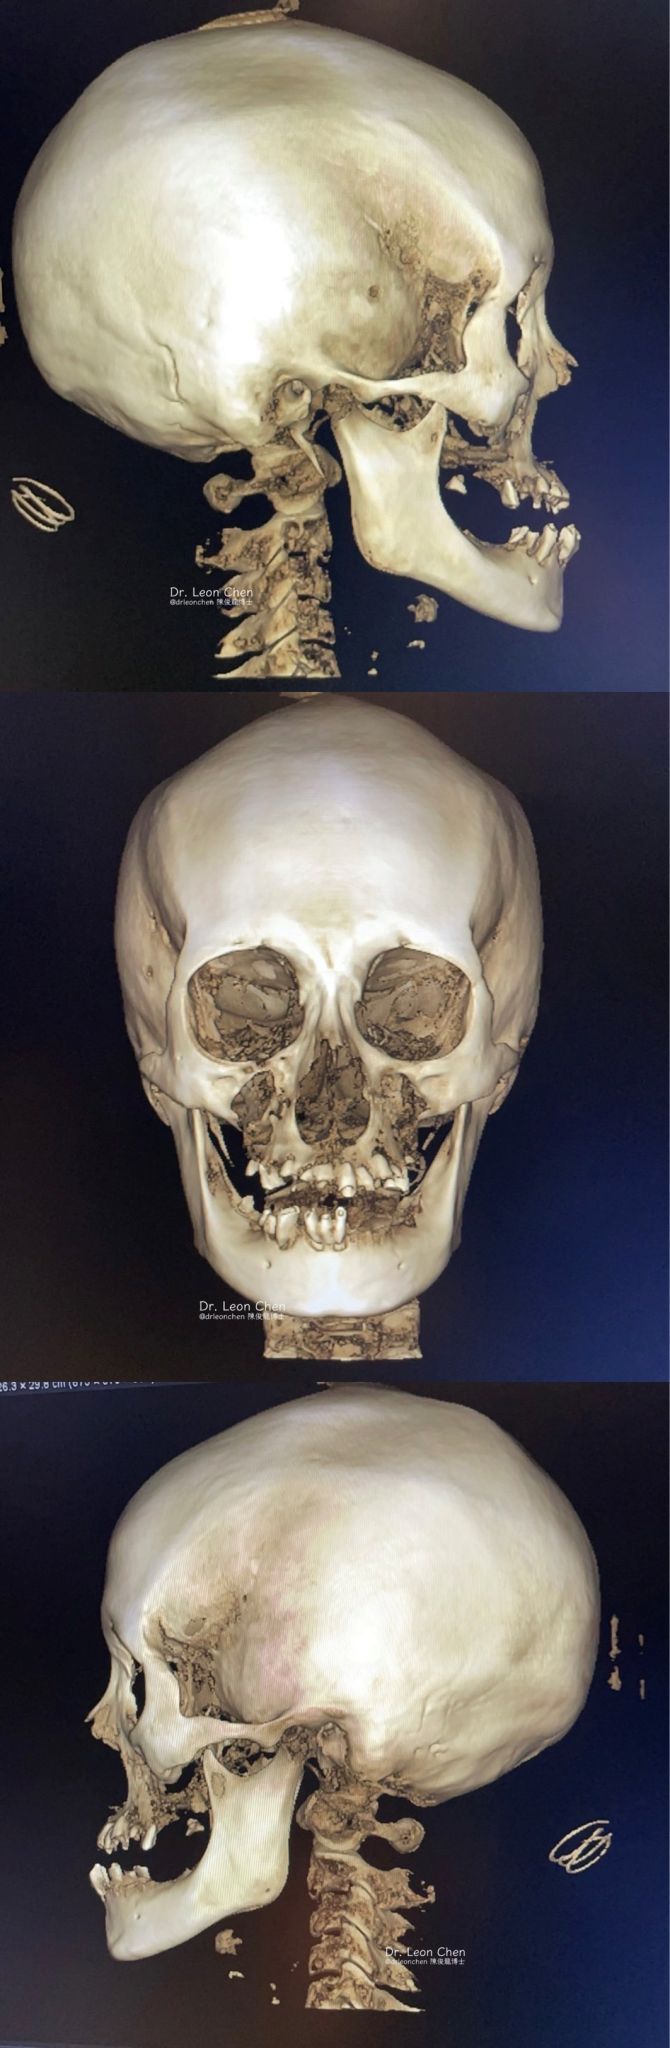

精奈創一鑽植牙系統團隊|從一口爛牙到重新微笑

一位新病人帶著滿口爛牙走進診所,在陳博士全口植牙後,當天「走進來一口爛牙、走出去就有全口牙」,可以正常飲食,完全不影響生活品質。

這位年輕病人經濟條件有限,因此採取最保守的六根植體的全口重建。這個方案更難做,要在沒有導板的情況下,還要保持完美地平行,展現出極高的臨床技術水準。

不要為了微小的修飾,讓病人承受更多痛苦。「他才24歲,牙齒會拖成這樣,一定是害怕看牙。」能在最短時間讓病人重新開口笑,這就是博士所謂「照顧病人的身心靈」。